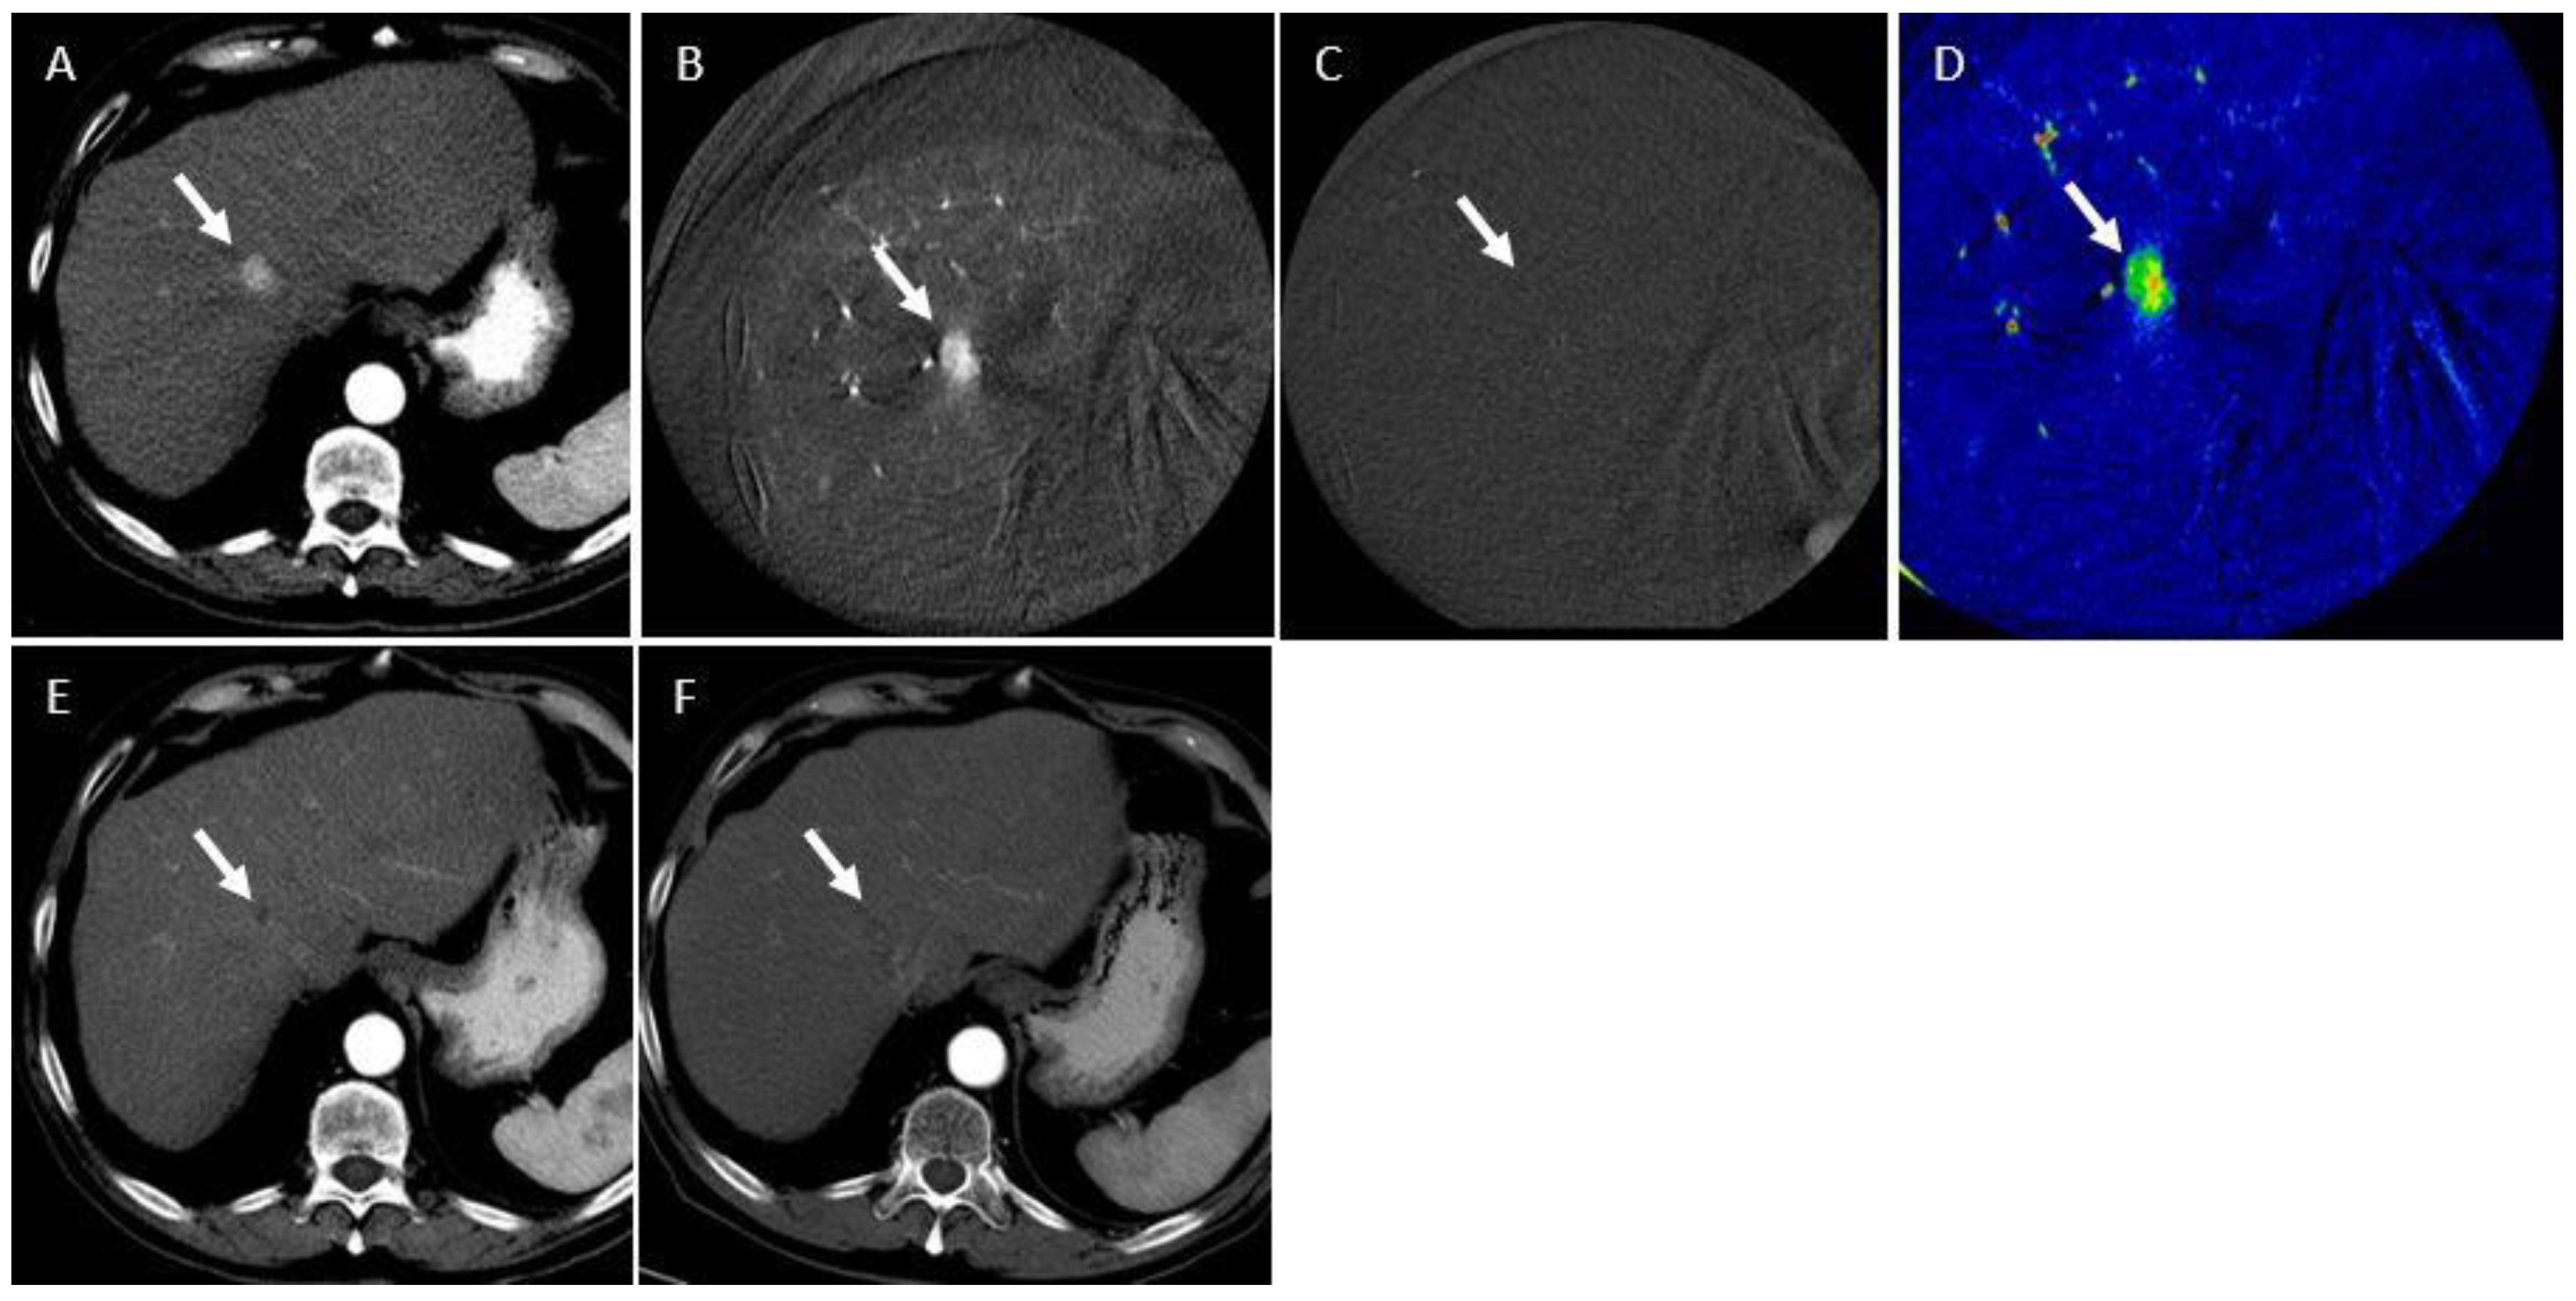

2.3. CBCT Acquisition and Contrast Injection

2.4. Calculation of Tumor Enhancement Parameters

2.5. Assessment of Treatment Response